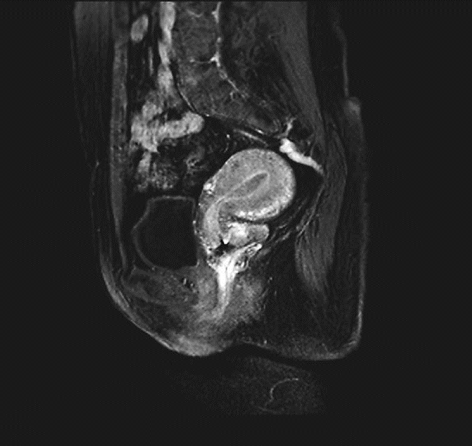

ⅠB1期宫颈癌MR ⅠB2期宫颈癌MR

ⅡA1期宫颈癌MR ⅡA2期宫颈癌MR

ⅡB期宫颈癌MR ⅢA期宫颈癌MR

ⅢB期宫颈癌MR ⅣB期宫颈癌MR